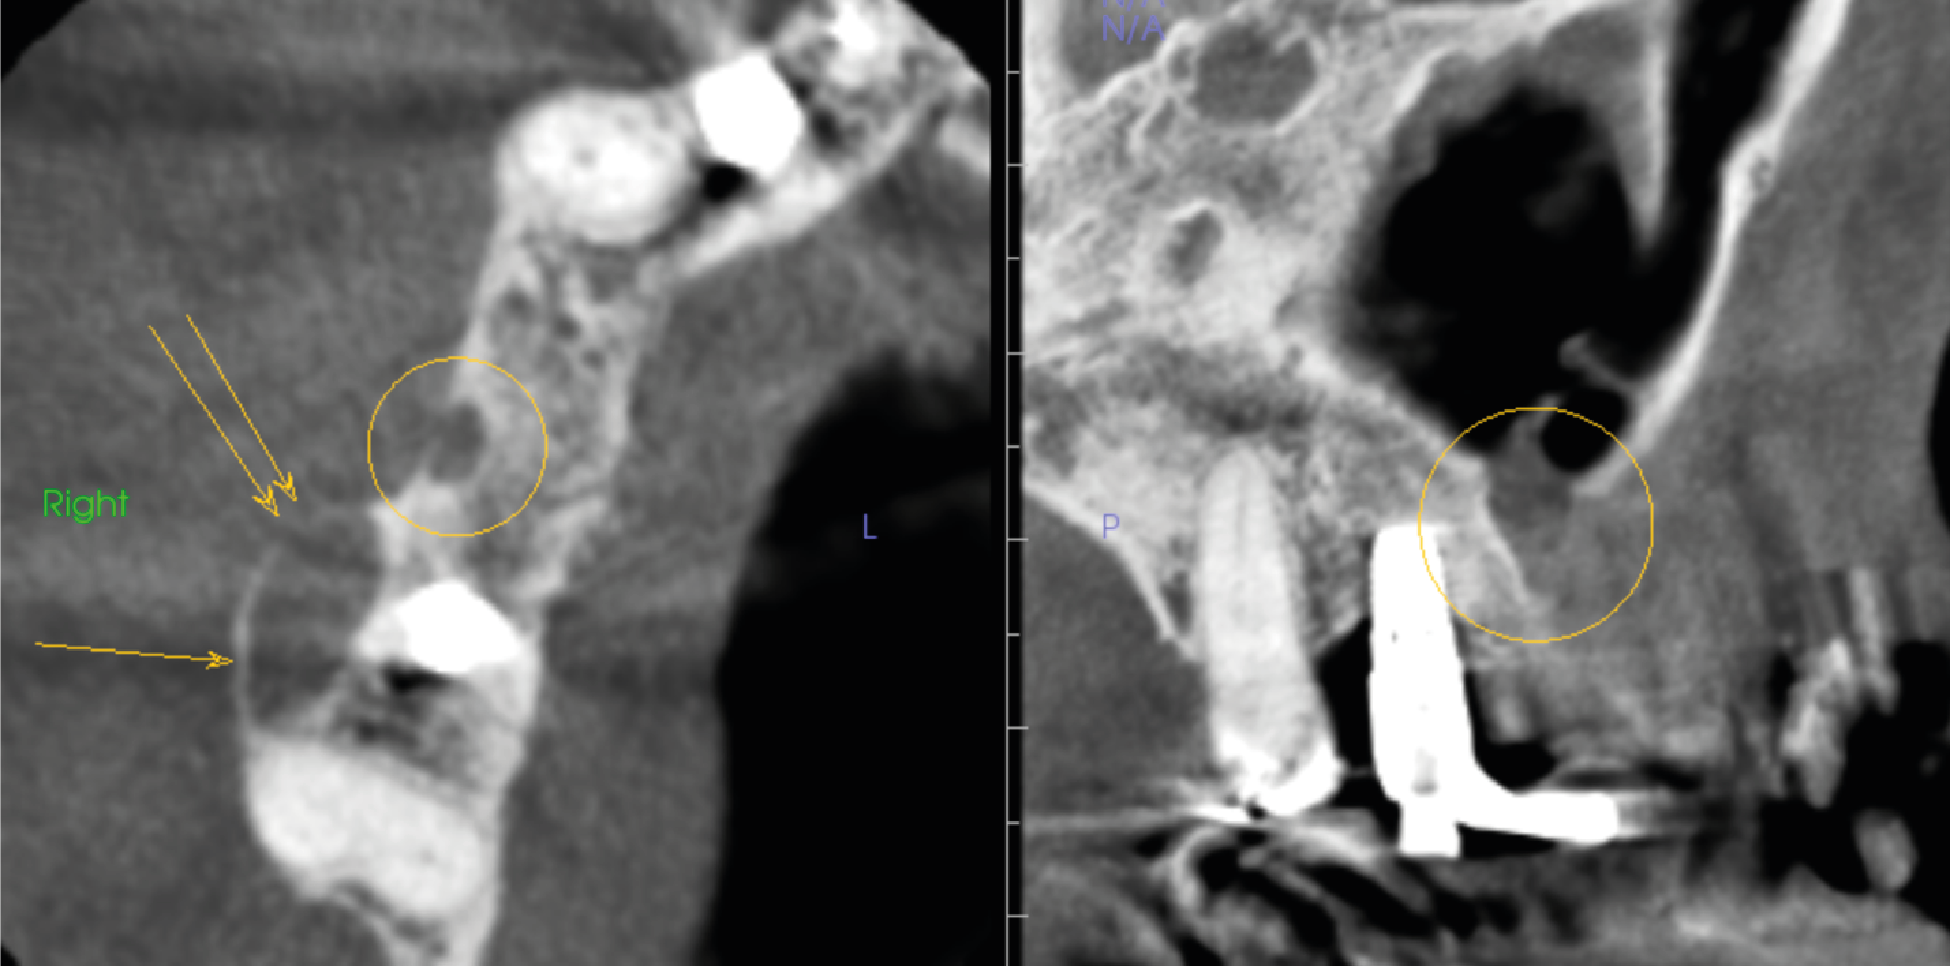

An axial slice (left image in Figure 2) shows an incomplete well defined unilocular radiolucency 3 x 2 mm in the buccal side of the alveolar ridge UR 5 edentulous region (circle in image). Just posterior in UR6,7 region there is a well-defined unilocular radiolucency 9 x 4 x 7 mm (single arrow) with loss of boney outline (two arrows). In the sagittal slice, right image of Figure 2, UR5 radiolucency shows a loss of the maxillary sinus boney floor.

Figure 2. Right image is axial slice through UR alveolar bone ridge with circle in UR5 region and arrows UR6 region. Left image is sagittal slice UR7 to UL3 region